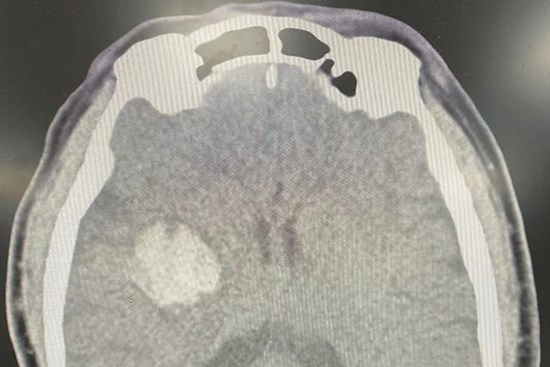

Người đàn ông 48 tuổi đang lái xe ô tô bất ngờ khởi phát cơn đột quỵ đã gây ra va chạm giao thông. Tại bệnh viện, bác sĩ xác định nam bệnh nhân bị nhồi máu não.